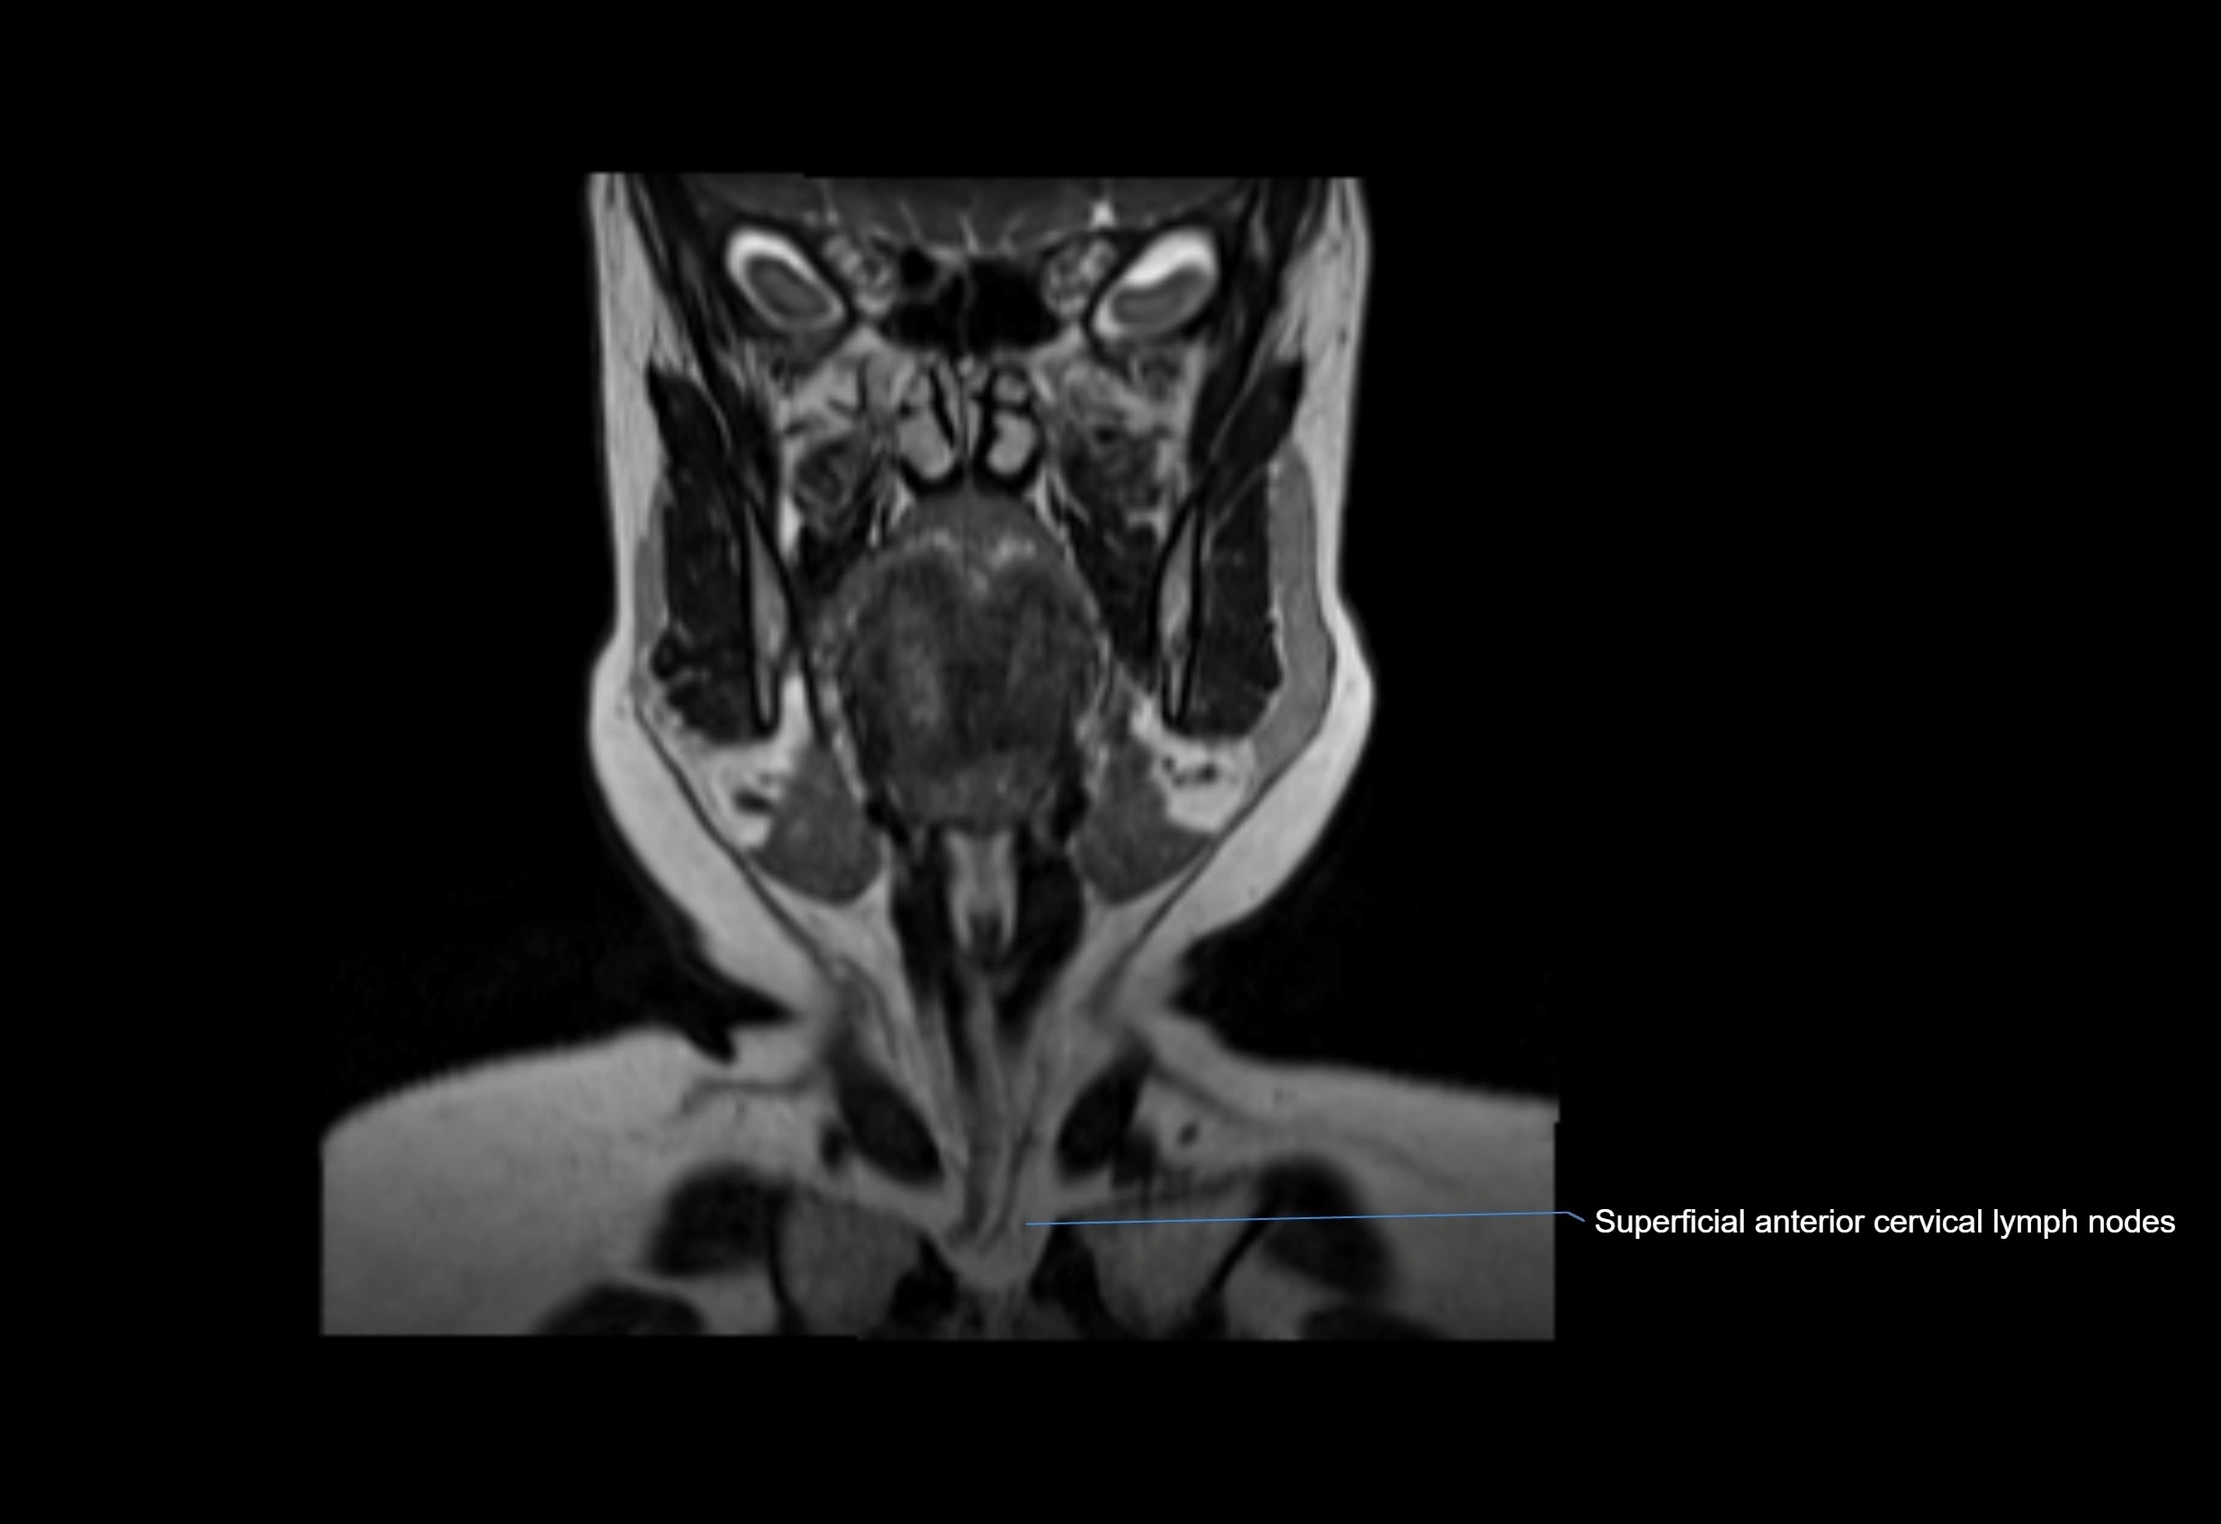

Location

• Found along primary lymph node chains, including preauricular, submandibular, parotid, and occipital regions

• Embedded in subcutaneous fat or superficial fascia, often lateral or posterior to primary nodes

• Variable in number; may occur unilaterally or bilaterally, depending on individual anatomy

MRI images

image